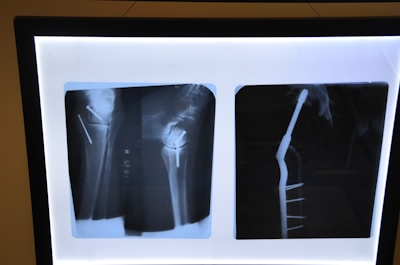

Two X-ray images display a side and front view of a medical fixture in a human bone. Metal pins and screws are visible, indicating a surgical procedure.